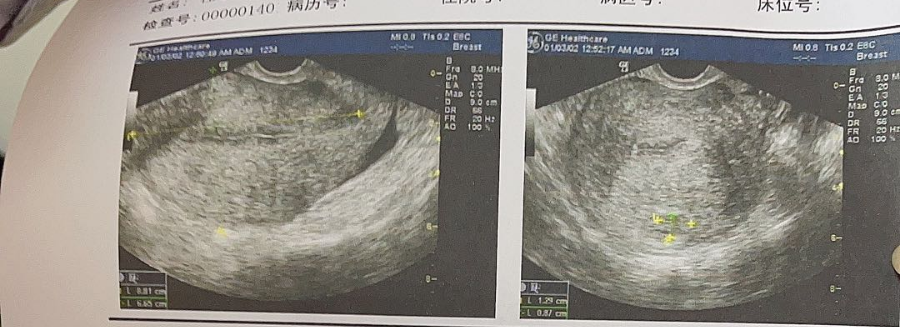

如果腺肌症患者的子宫太大,子宫腔超过9cm深,这时候上曼月乐环就不是特别合适了,容易出现脱环和环下移。环脱落的原因一方面是子宫腔太大,另一方面子宫腺肌症肌壁非常硬,它不像一个正常肌性的器官那么柔软,环在其间不容易附着,所以来月经的时候容很易被冲掉。